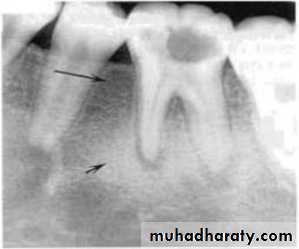

Blending border into adjacent area –gradual transition-normalappearing bone & abnormal appearing trabeculae -sclerosing osteitis• Invasive irregular border-bone destruction-malignancy.

Blending border. A gradual transition from the dense trabecular of sclerosing osteitis (short arrow) to the normal trabecular pattern (long arrow).• C:Shape